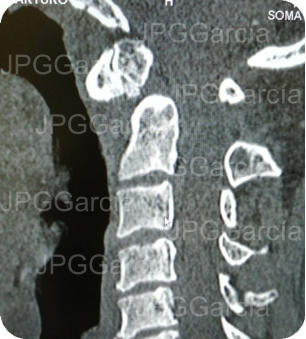

ESTUDIOS RADIOGRÁFICOS PREQUIRÚRGICOS

Imágenes de tomografía la unión cráneo cervical que muestra un fractura de la apófisis odontoides llamada “os odontoideo”